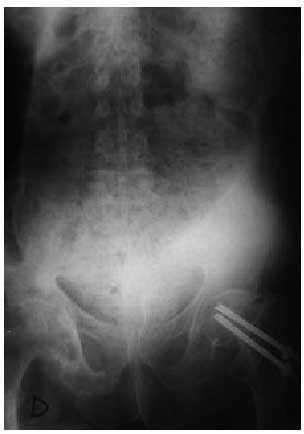

Fig. 1. Radiografía de abdomen. Se aprecia una enorme dilatación del rectosigma, con un diámetro de 22 cm.

Se realizó una radiografía de abdomen en la que se apreció una enorme dilatación del rectosigma con abundantes heces. El diámetro del asa era de 22 cm (fig. 1).